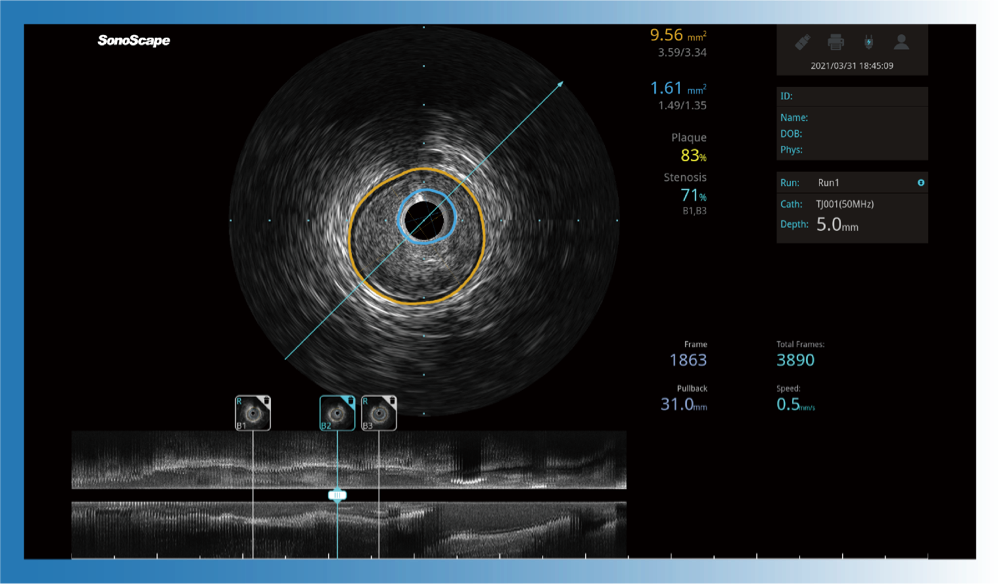

治療前后兩次測量錄像對比

簡化療效評估

一鍵智能描跡,自動測量斑塊負(fù)荷、面積狹窄率等指標(biāo),準(zhǔn)確率高于90%